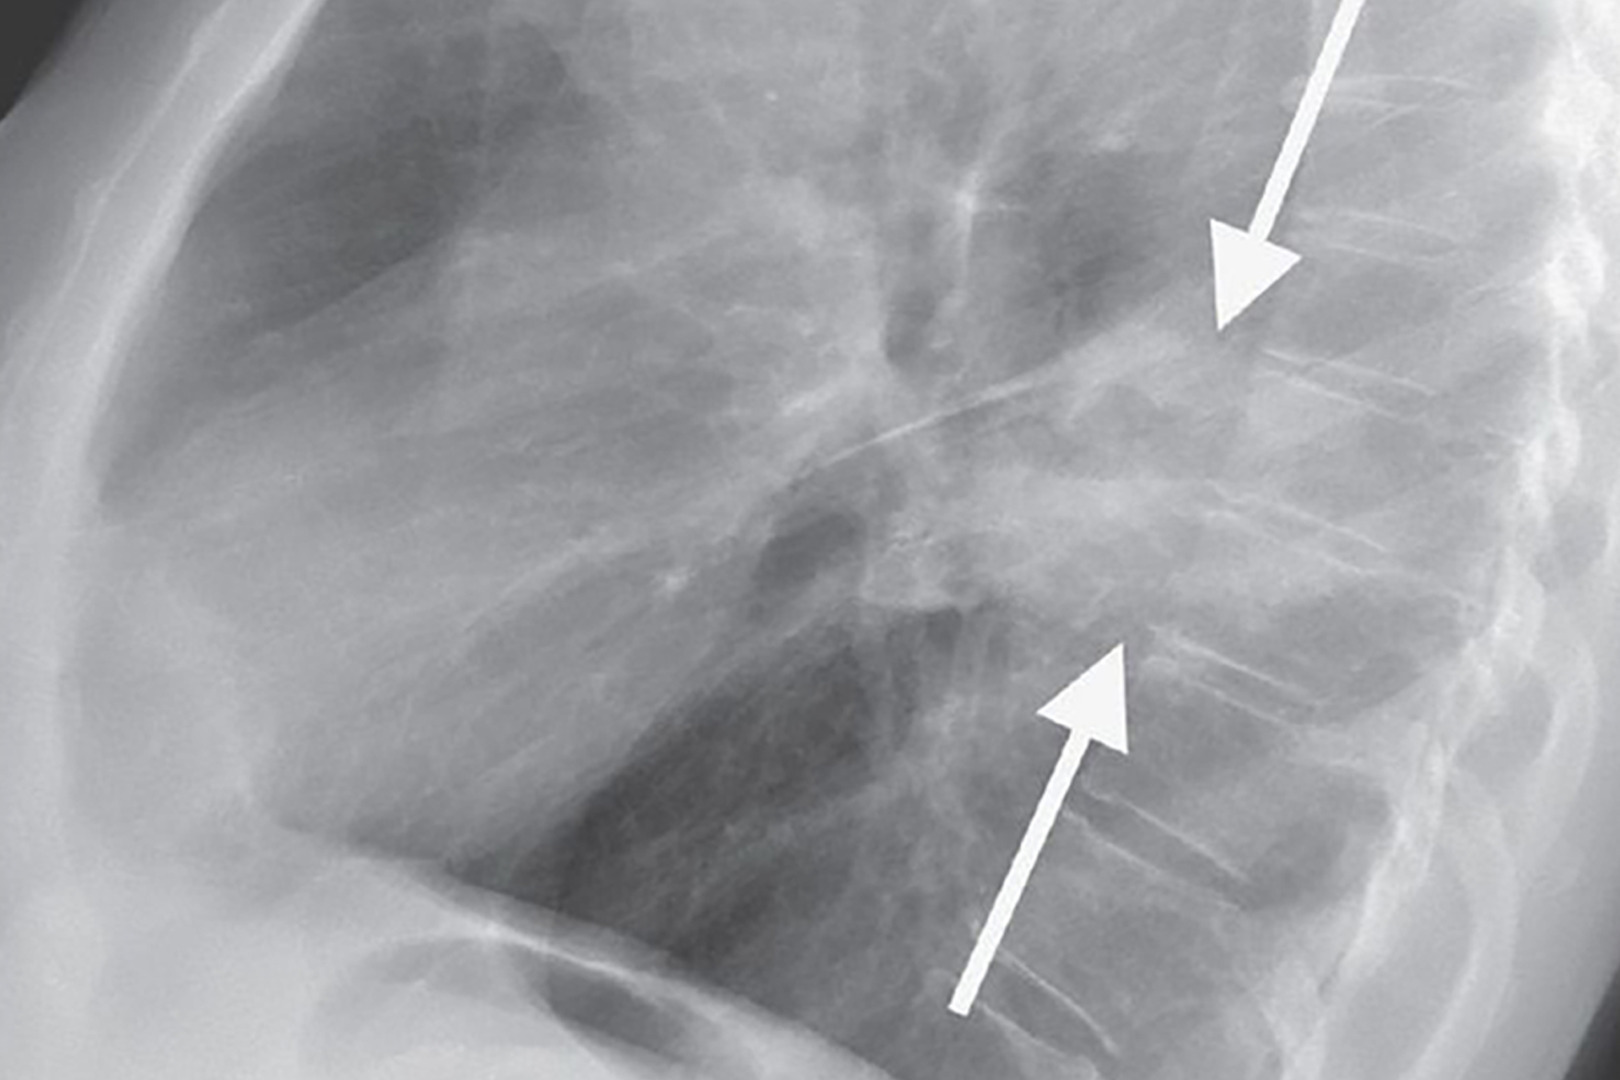

Diagnosis starts with a thorough medical history, physical examination and imaging studies. Chest X-rays are often the first step, but CT scans provide more detailed images and can detect smaller nodules more effectively. PET-CT may be used to see if the tumour is metabolically active in the lung or elsewhere.

Lung function tests help determine overall respiratory health, and blood tests may give clues about general well-being. A biopsy via bronchoscopy, CT-guided needle, or surgical sampling is necessary to confirm if the abnormal tissue is lung cancer. Pathologists examine the tissue under the microscope, and molecular testing may be added to guide targeted therapies.